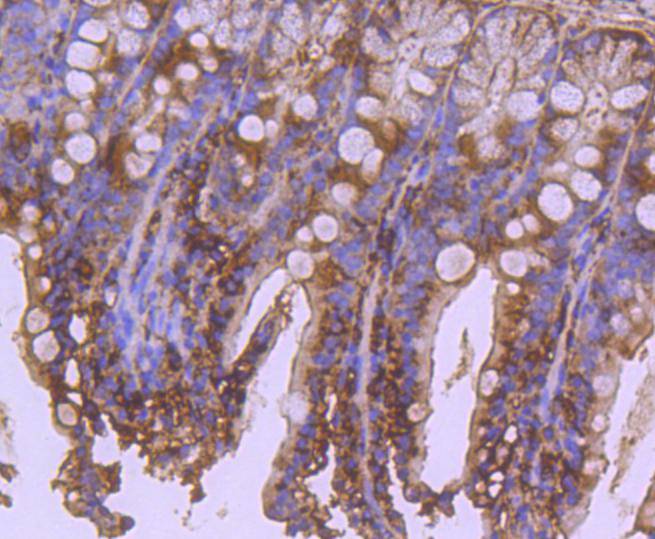

- 抗体名:

Apaf-1 Rabbit mAb

- 应用范围:

WB, ICC/IF, IHC

applications

appl_detail

WB: 1:1,000

IHC: 1:50-1:200

ICC: 1:50-1:200